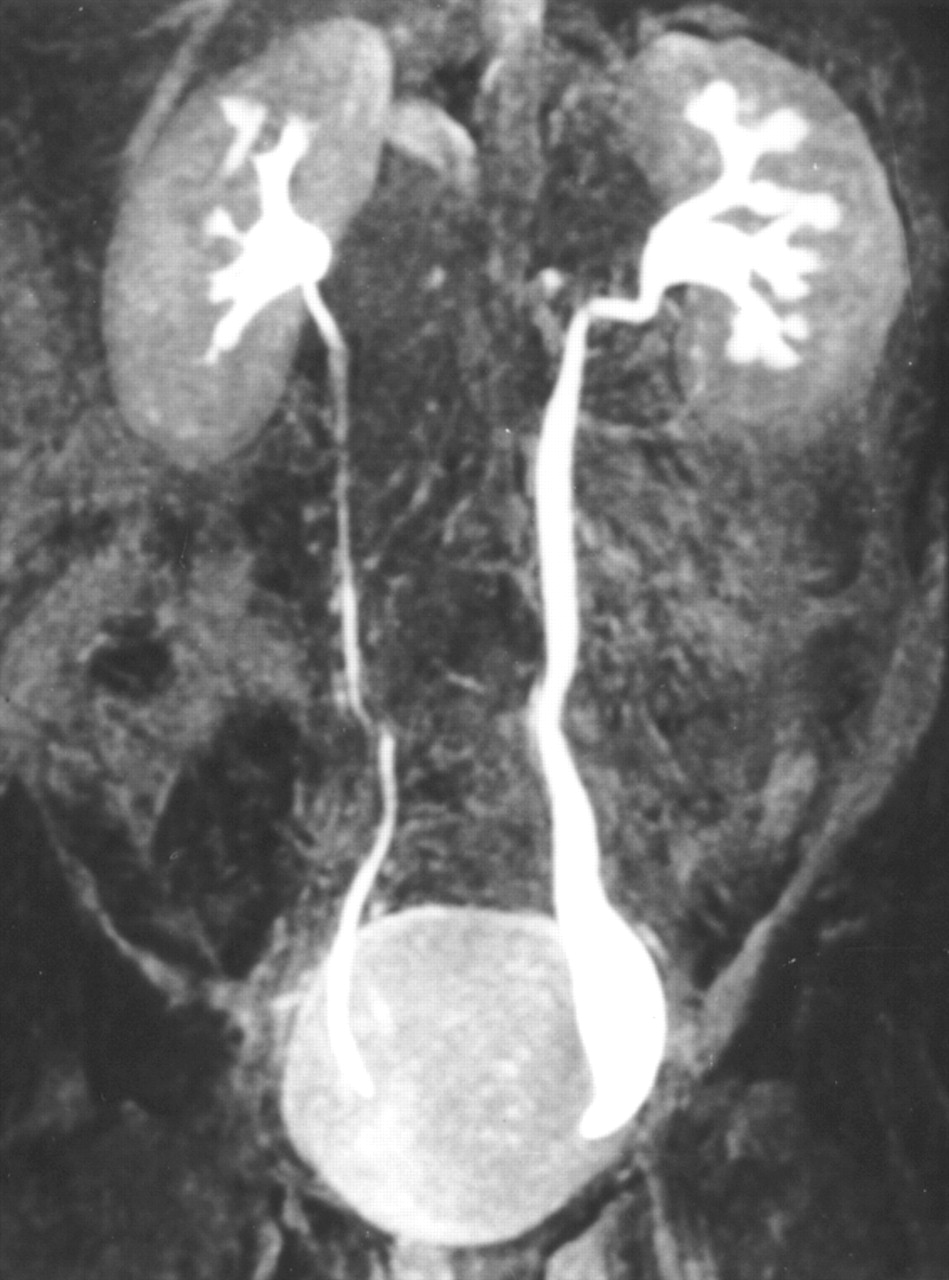

Per megauretere in campo medico, si intende un'anomalia che riguarda la grandezza dell'uretere che risulta più ampio della normale condizione.